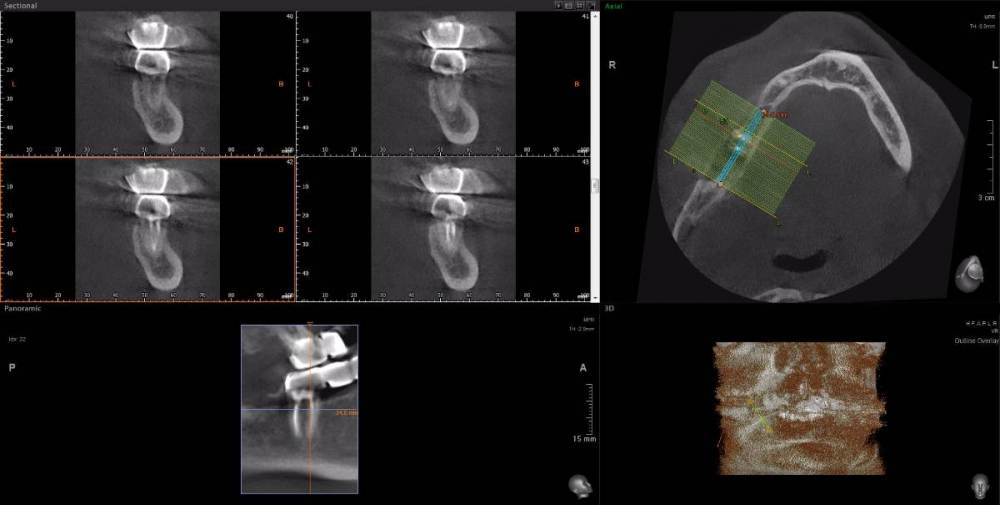

Dude Опубликовано 1 апреля, 2021 Поделиться Опубликовано 1 апреля, 2021 По плану в 1 этапе, кроме остального: лечение каналов и укрепление их стекловолоконными штифтами: 16, 25, 27, 44, 47; имплантация 14, 15, 17, 12, 11, 21, 22, 24, 26, 36, 37, 46, 45. Во 2 этапе (через 5-6 месяцев) установка коронок. Лечение в другой стране. Чтобы сократить длительность первого этапа, предложили лечение зубов сделать на 2 этапе. Очень засомневался, можно делать имплантацию с невылеченными зубами? Ссылка на комментарий

Dude Опубликовано 1 апреля, 2021 Автор Поделиться Опубликовано 1 апреля, 2021 https://disk.yandex.ru/d/6d0pmZ1zArn1Og Так? Ссылка на комментарий